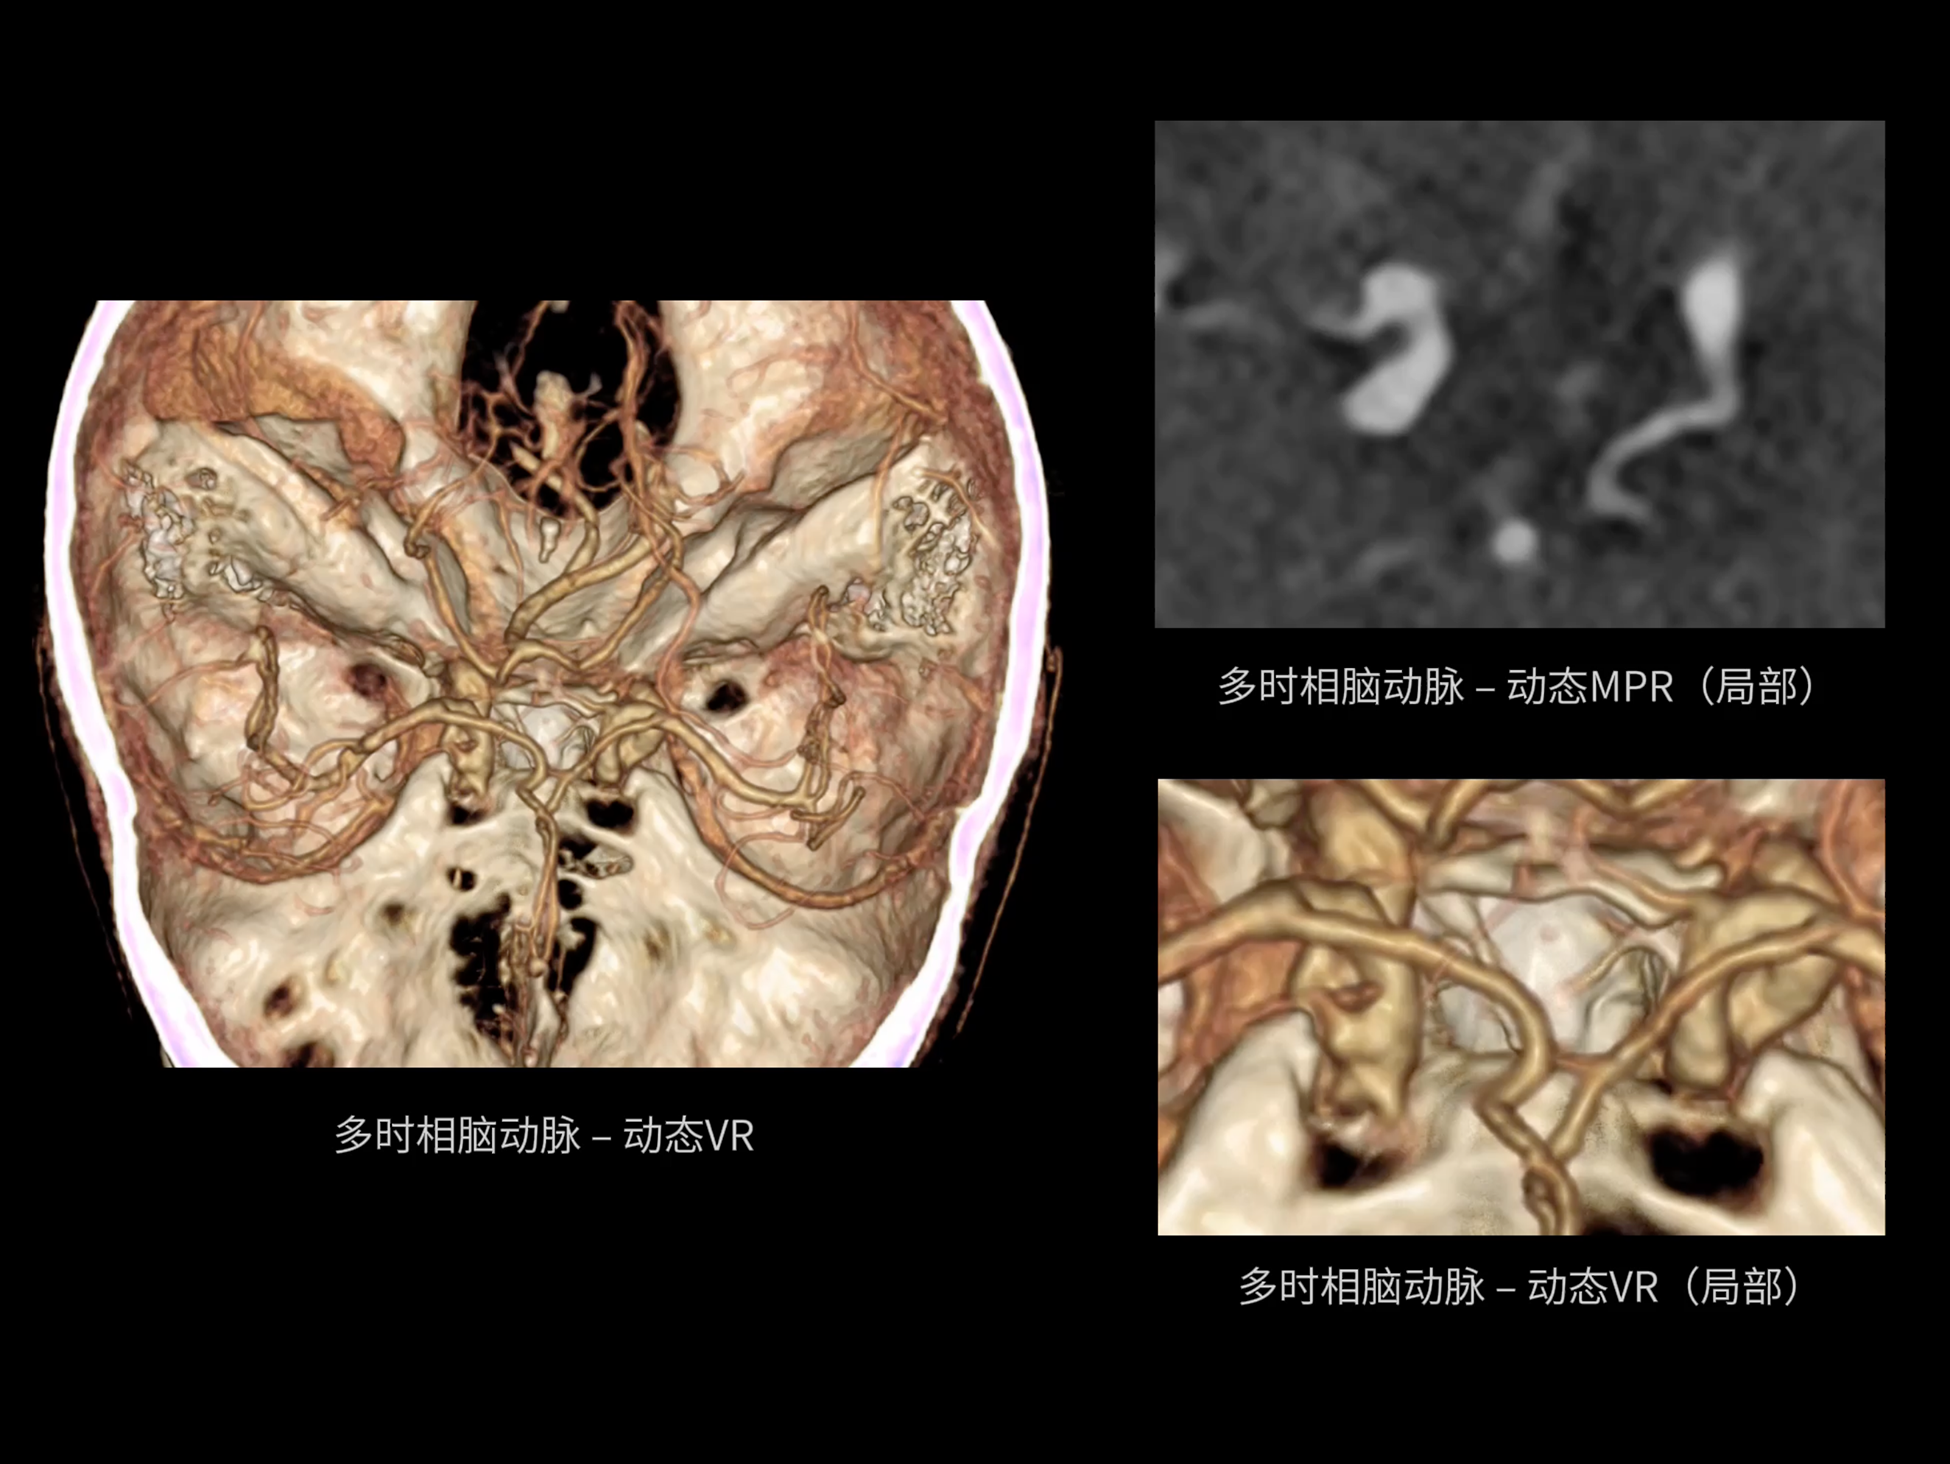

uCT SiriuX® 以16cm超宽Z轴覆盖,使超高时间分辨率应用于完整器官成像。无论是心脏搏动还是关节运动,整个目标区域可在同一瞬时被完整、清晰地捕捉,彻底消除时序误差,实现从“局部瞬间”到“全器官瞬时”的成像跨越。

全器官同步

全域能谱

uCT SiriuX® 依托16cm超宽探测器与双源能谱技术,实现真正意义上的全身高清能谱成像。单次扫描同步获取灌注、能谱等多维定量参数,精准解析组织特性与病灶成分,为临床决策提供更深层次的诊断依据。

全身高清能谱成像

uCT SiriuX® 采用独有的双宽体探测器设计,实现470mm超大视野与全脏器容积覆盖的能谱成像,轻松应对不同体型患者和扫描部位应用需求。配合创新能谱重建影像链与精准双能数据配准,系统可有效抑制伪影、提升信噪比,在全脏器范围内提供高质量能谱图像,显著拓展临床精准诊断的广度与深度。